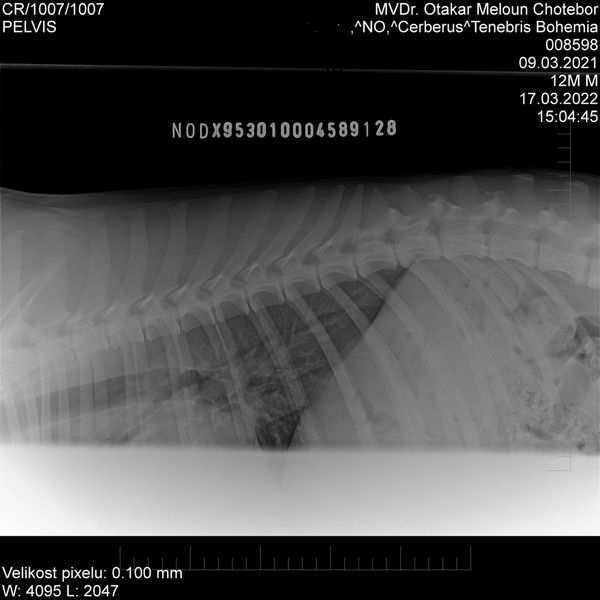

HD: A

ED: 0/0

Spondy: Free